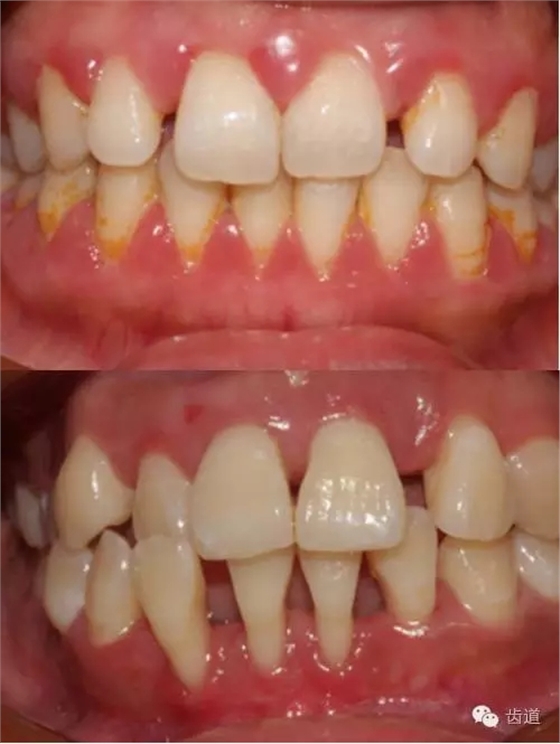

1、口腔衛(wèi)生狀況及局部刺激物(牙菌斑、牙石,不良修復(fù)體)

牙石及不良修復(fù)體

2、牙齦

(顏色、形狀、質(zhì)地、退縮、BOP、PD、附著齦)